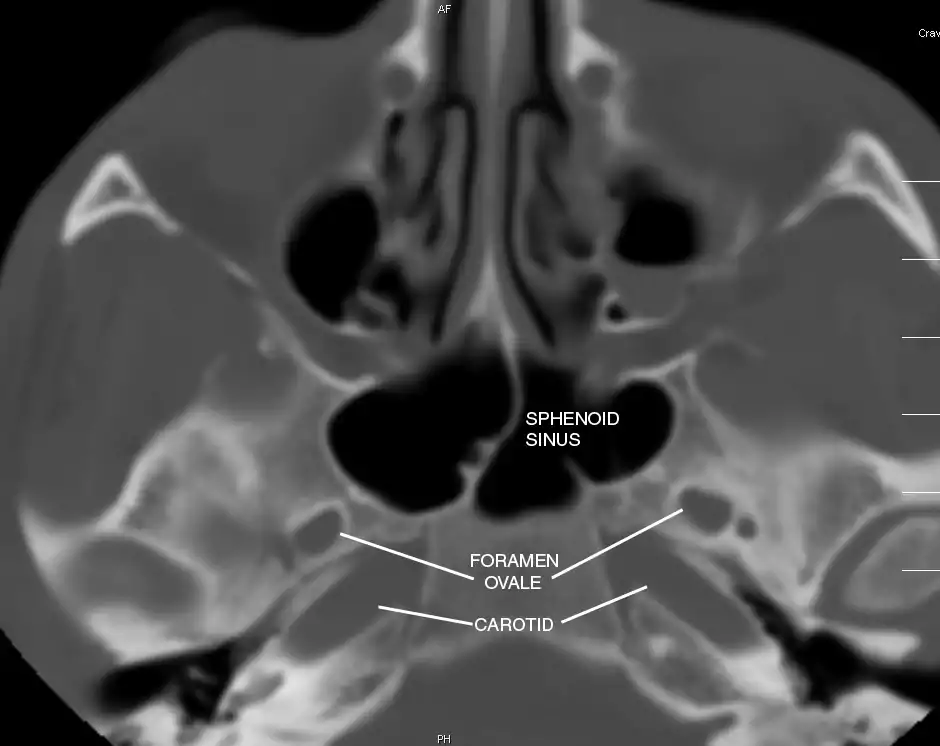

Sphenoid Sinus has 12 close structures: II, III, IV, V1, V2, VI, Vidian Nerve, Carotid artery, Brain, Dura, Pituitary.

- V2 = Maxillary division, Trigeminal Nerve: exits foramen rotundum, superomedial to V3's foramen ovale.

- C = Carotid Artery: often with bony dehiscence into sphenoid. Together with CN II forms opticocarotid recess.